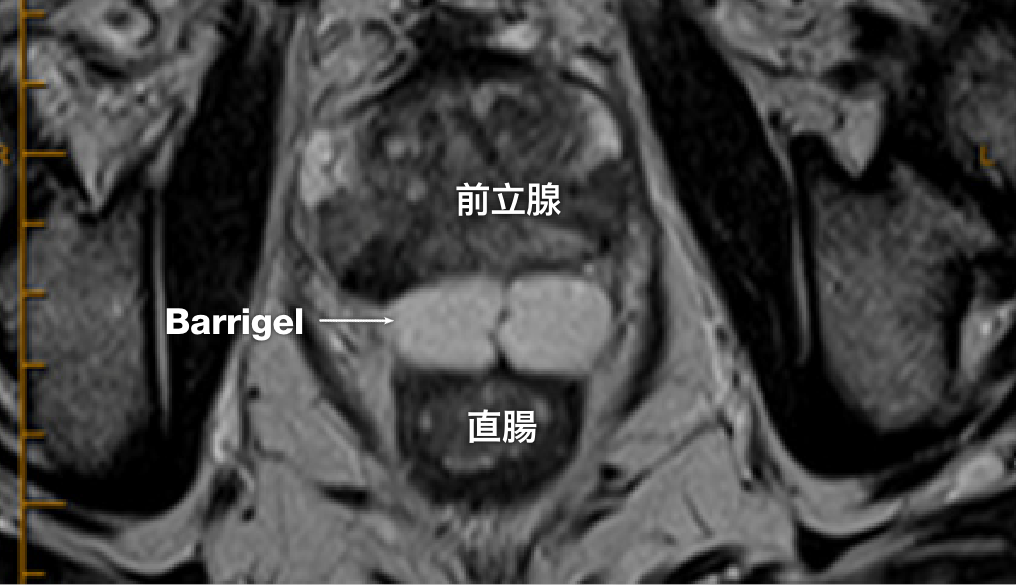

MR 画像

MR画像提供:Prof Michael Chao, MBBS (Hons), FRANZCR, AFRACMA, DMedSc, Radiation Oncologist; Victoria, Australia